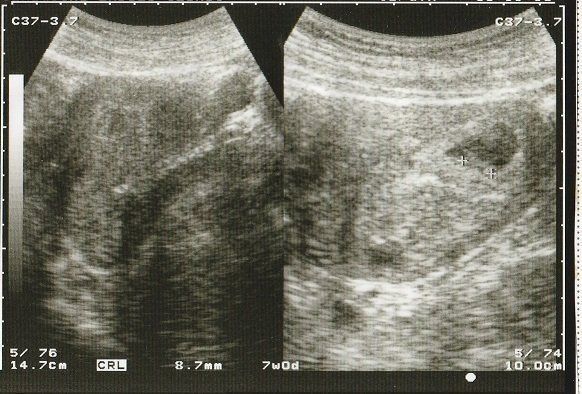

妊娠7週目のエコー写真 徐々に大きくなっていく胎芽

妊娠の喜びととともに不安も大きかった日々。毎週病院で検査してもらい、徐々に成長している過程を確認して、ホッと胸をなで下ろしていました。